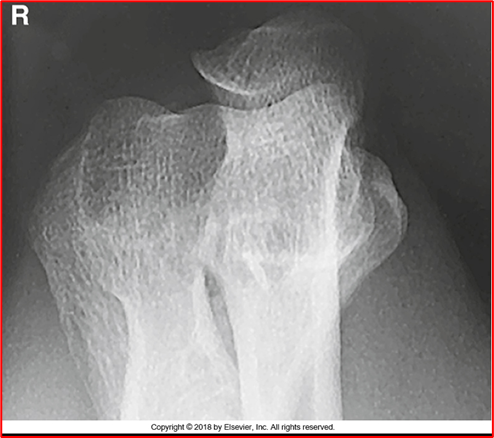

-Radius and ulna should be completely separated (almost there but not fully)

-There is crowning of the radial head (should NOT be present, should be flat) meaning they are not fully extended

-Capitulum and radial head present

-REPEAT because of crowning

critique this lateral oblique elbow image